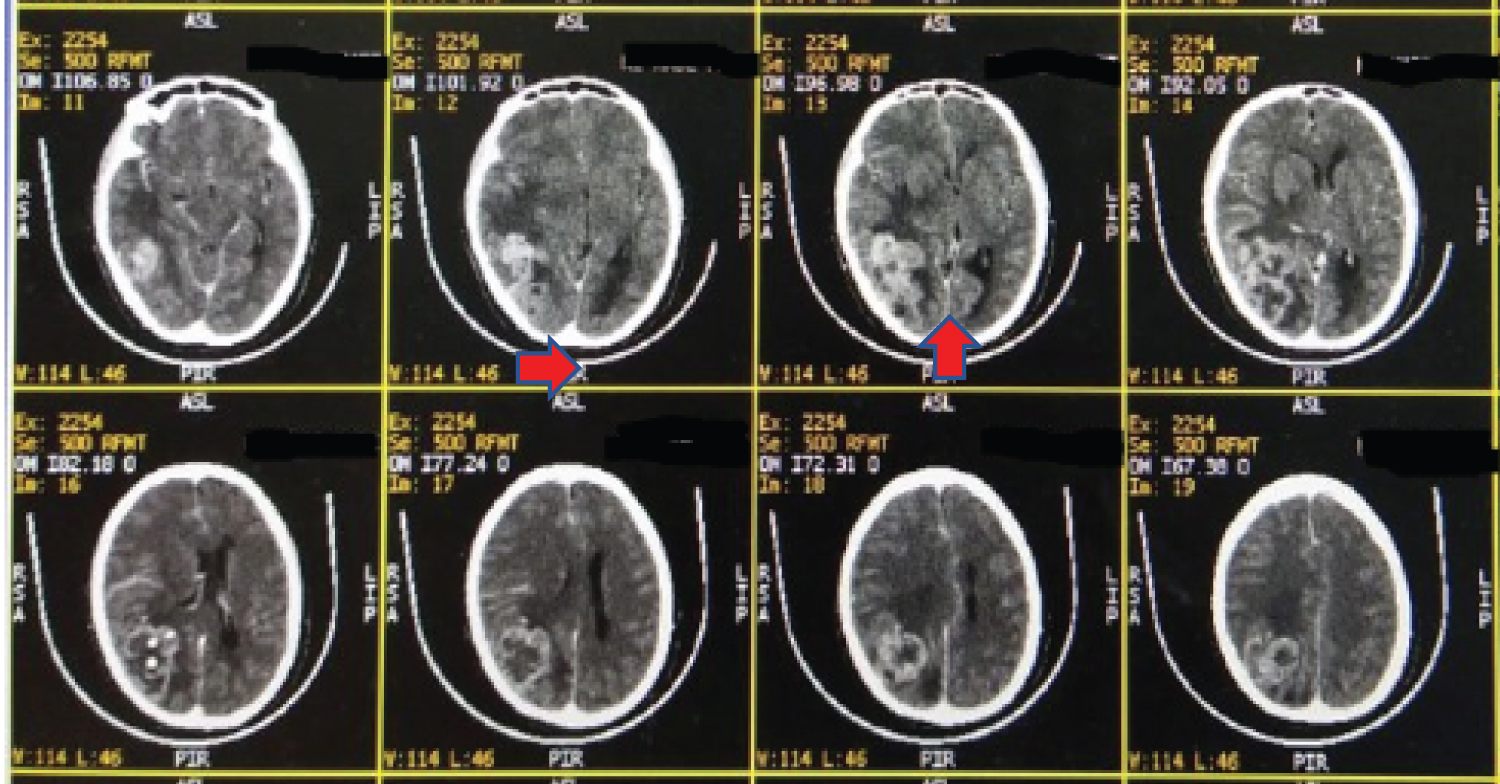

A 63-year-old female presented with progressive headache and visual disturbances in the last two months before admission. She also complained of a limp on the left side in the previous two weeks and was progressive until she couldn't lift her extremities. Vomit is also presented at the time she was admitted to the hospital. General physical examination revealed bilateral visual acuity 1/300, cranial nerve deficits, motor deficits shown as left flaccid hemiparesis, and positive Babinski reflex on the left foot. CT scan with the administration of contrast was done (Figure 1 and Figure 2) and showed a single iso-dense lobulated supratentorial intra-axial solid mass, defined by the irregular border with a distinctive central necrotic and multiple calcified components, measured +/- 5.9 × 4.6 × 4.9 cm, which after contrast administration showed enhancement ring on the right parietooccipital lobe, accompanied by vasogenic edema area, leading to narrowing of the anterior-posterior horn of the right lateral ventricle, third ventricle, and right ambient cisterna, and causing midline shift to the left of +/- 1 cm, suggesting a primary malignant brain tumor, suspected high-grade astrocytoma, calcification of the falx cerebri in the posterior aspect, hypo pneumatization accompanied by left mastoiditis, hypo-pneumatization accompanied by bilateral sphenoid sinusitis. The tumor was resected, and histopathological analysis showed tumor mass with increased cellularity consisting of the proliferation of neoplastic cells forming a diffuse pattern. These neoplastic cells with oval to spindle spherical morphology, mild-moderate pleomorphic nuclei, hyperchromatic, partially with visible nuclei. Mitotic rate showed 14 per 10 high-power fields. Nuclear holes and pseudo-inclusion are visible. The proliferation of blood vessels, tumor cells surrounding the geographic necrosis area, dilation of blood vessels, and bleeding are also visible in this tissue. In another focus, it appears that neoplastic cells are arranged in irregular fasciculus with spindle morphology, narrow eosinophilic cytoplasm, pleomorphic, irregular nuclear membrane, hyperchromatic, partly vesicular chromatin with visible sub-nuclei, and clear cytoplasm (clear cell). The morphology's conclusion follows atypical meningioma (WHO grade II) as shown in Figure 3 and Figure 4.

Figure 1: CT scan without contrast showed a single iso-dense lobulated supratentorial intra-axial solid mass, defined by the irregular border with an irregular central necrotic and multiple calcified components, measured +/- 5.9 × 4.6 × 4.9 cm. View Figure 1

Figure 2: CT scan with contrast showed that enhancement ring on the right parietooccipital lobe, accompanied by vasogenic edema area causing midline shift to the left of +/- 1 cm, suggesting a primary malignant brain tumor, suspected high-grade astrocytoma. View Figure 2

This case showed the CT scan was a single iso-dense lobulated supratentorial intra-axial solid mass, defined by the irregular border with a distinctive central necrotic and multiple calcified components, which on contrast showed enhancement ring contrast, on the right parietooccipital lobe, accompanied by vasogenic edema area, suggesting a primary malignant brain tumor, suspected high-grade astrocytoma. Meningiomas are extra-axial lesions in which CT scan showed intralesional calcification and bony changes. The location of cancer can be seen along the convexity, also generally present as a solitary lesion [7,8]. Imaging atypical meningiomas WHO grade II or meningiomas WHO grade III have a wide range; hence, it is tough to differentiate them solely based on clinical and imaging like the case above. Based on the literature, the imaging of meningiomas WHO grade II and WHO grade III is extra-axial mass with irregular demarcation, intratumorally necrotic areas, extensive brain edema, and changes of the bone. Histopathology analysis is the gold standard to differentiate them well [4,7].